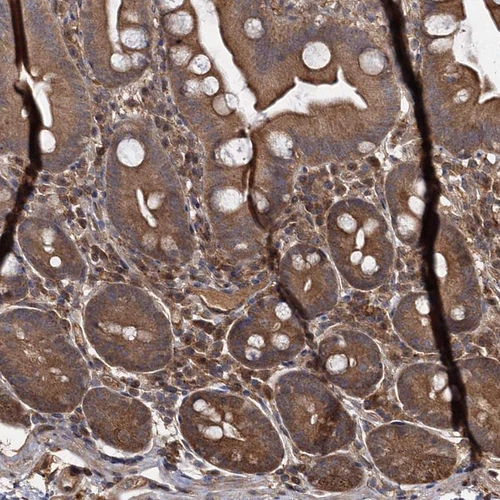

Immunohistochemical staining of human liver shows moderate cytoplasmic positivity in hepatocytes.